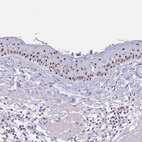

Immunohistochemical staining of human skin shows strong positivity in nucleoli in squamous epithelial cells.